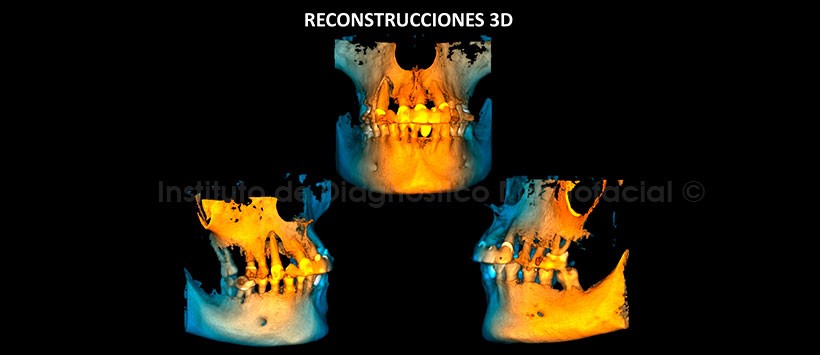

En las reconstrucciones 3D se observan la pérdida de la tabla ósea vestibular y la perdida de soporte óseo periradicular (Figura 6 y 7).